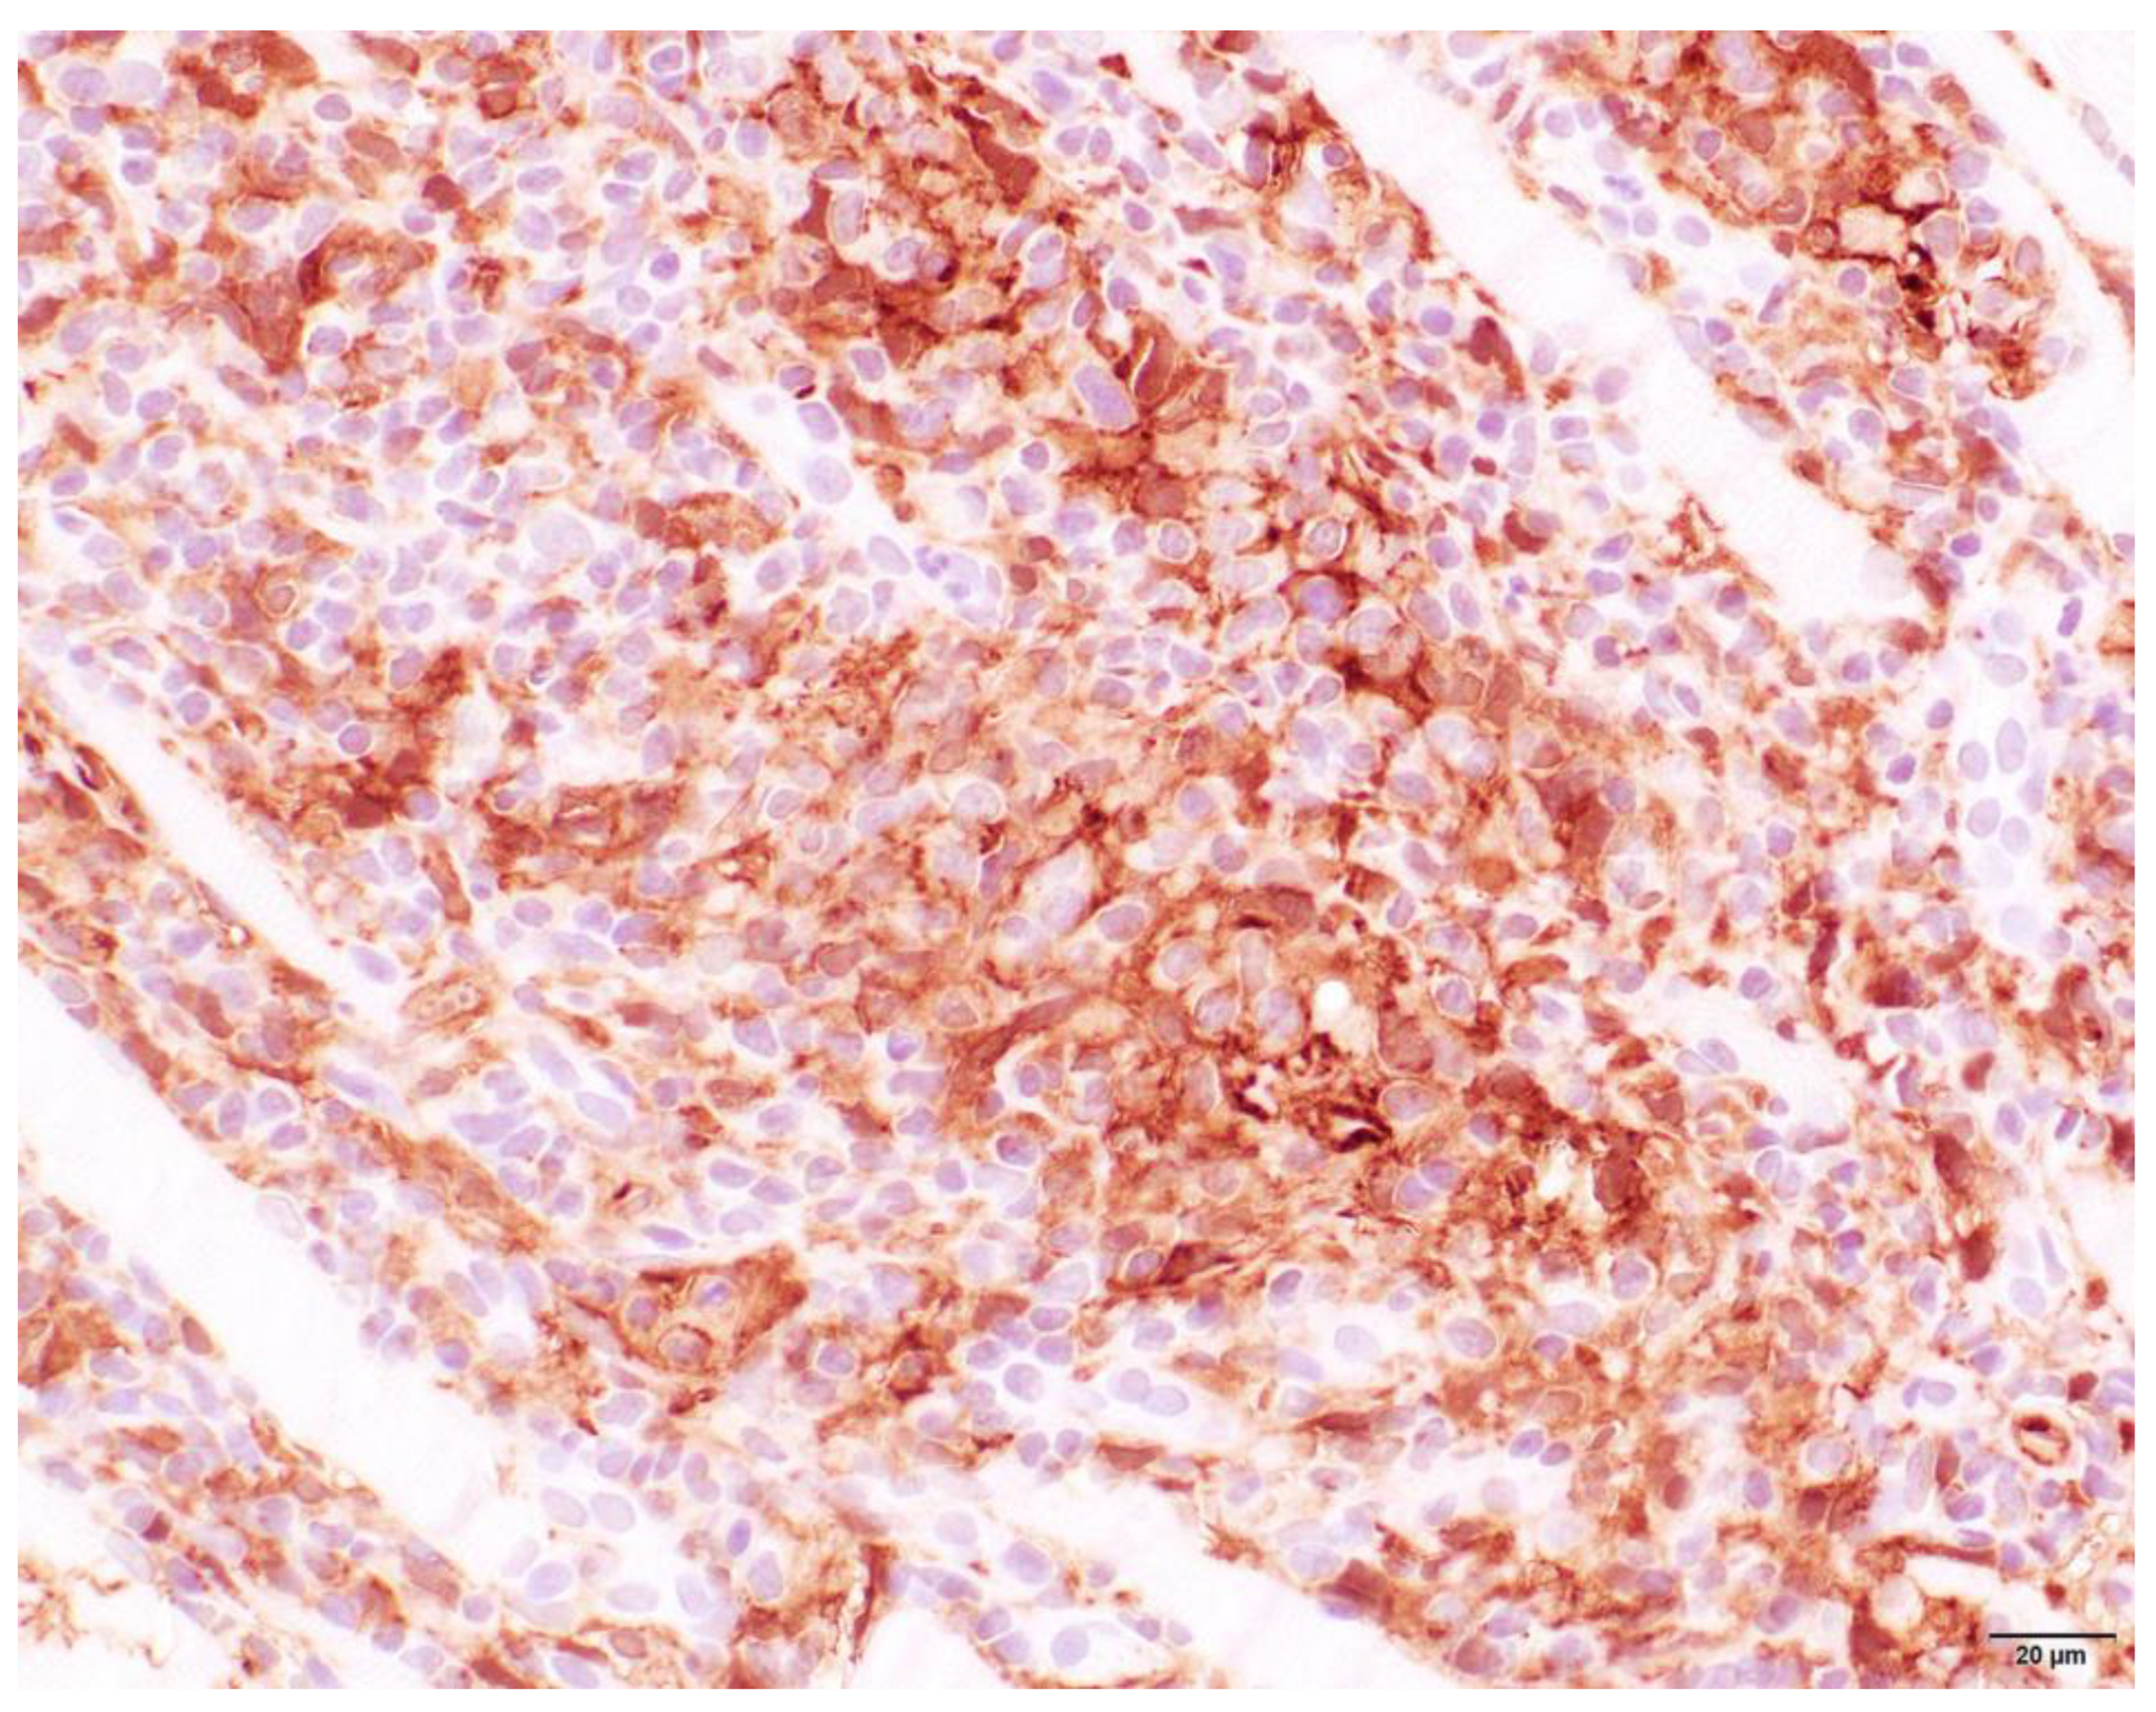

3.4. Histopathology